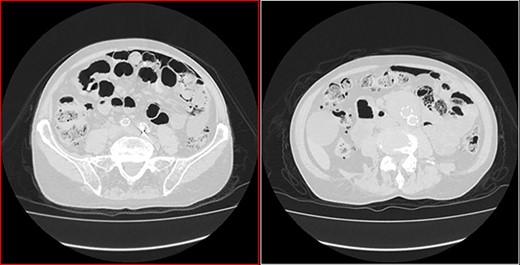

He arrived at the emergency department walking and with no clinical distress. He was complaining of hematuria for a month and worsening of chronic constipation in the last 2 days. Physical examination demonstrated discrete abdominal distention. Laboratory tests showed normal c-reactive protein (CRP), white blood cell count and lactate level. A new CT revealed no change in the previous findings: intestinal pneumatosis and pneumoperitoneum (Figs 2 and 3).

Transversal CT image in lung window showing pneumoperitoneum and pneumatosis intestinalis.